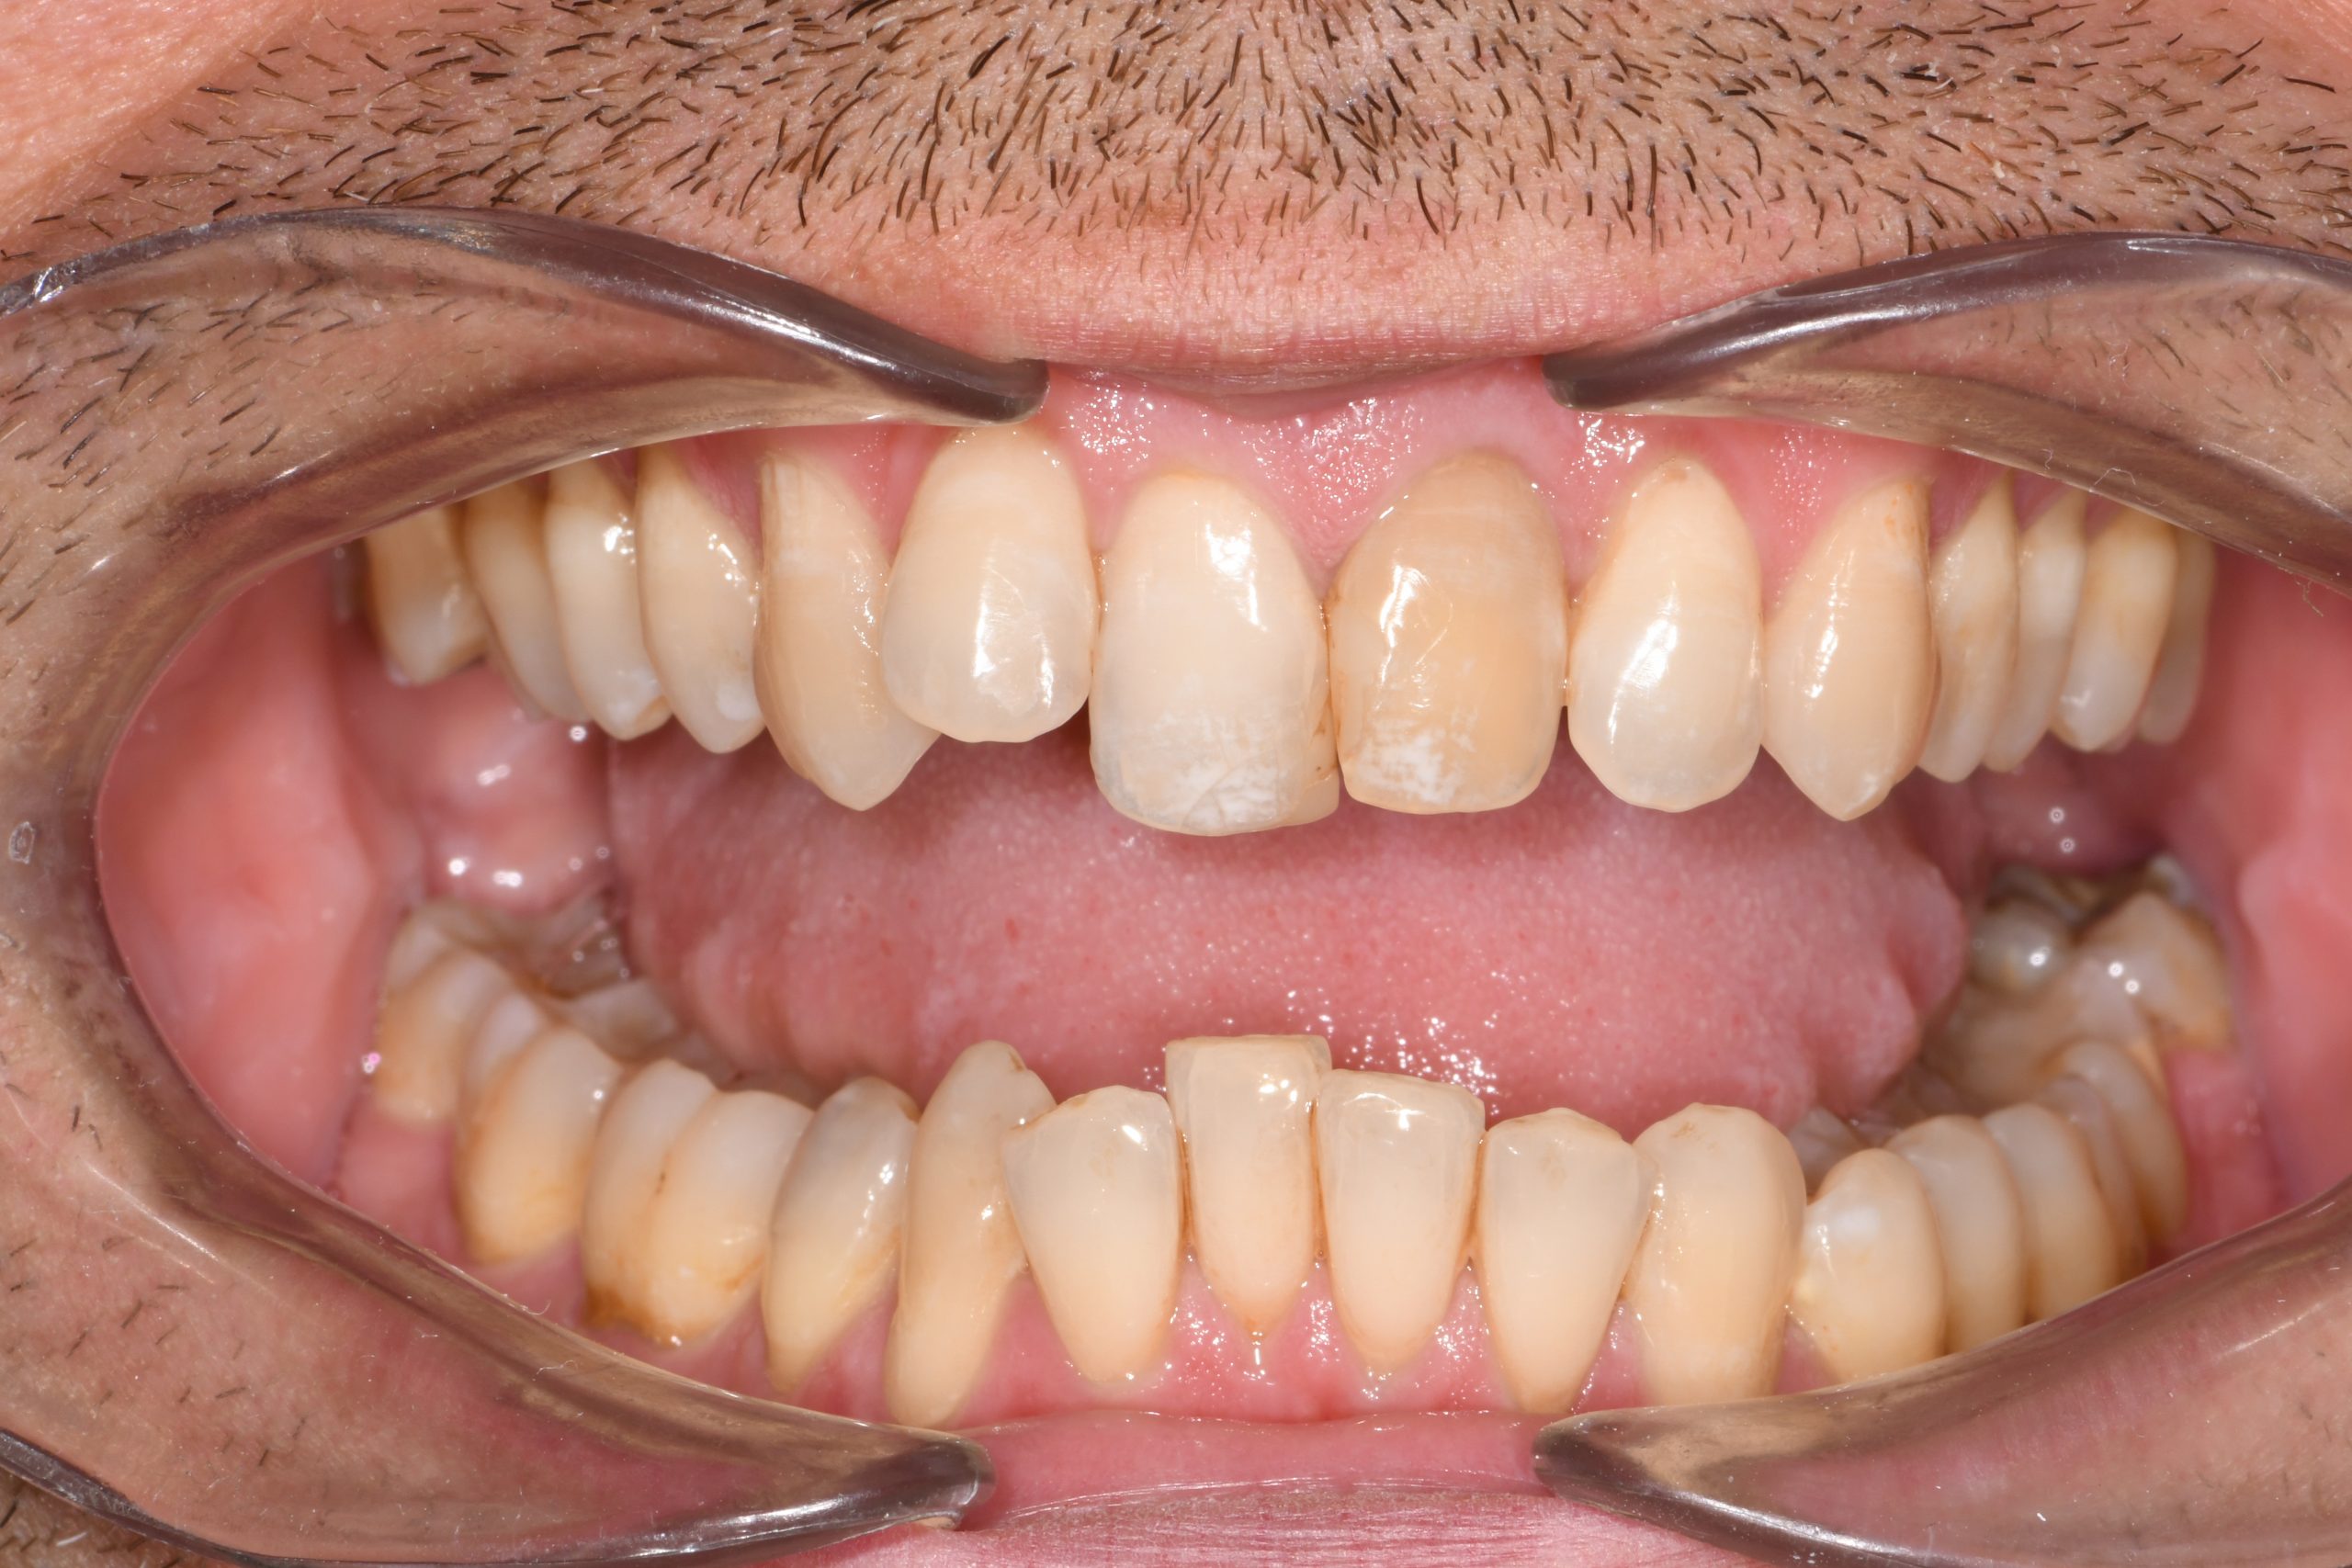

Az elmúlt évekből rengeteg szakmai referenciát tudnánk bemutatni, amelyek különböző fogszabályozási problémákat oldottak meg. Válogatva a több száz esetből, ezen az oldalon olyan képeket, információkat igyekeztünk bemutatni, amelyeknek a segítségével a jövőbeni pácienseinknek azt tudjuk üzenni: A Te fogsorod is lehet gyönyörű!

(Képeket a Pácienseink külön írásos beleegyezésével mutatjuk be!)